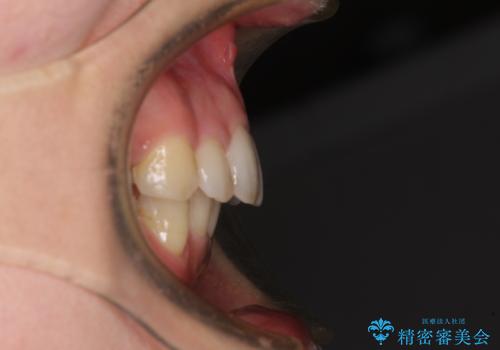

閉じにくい口元 前歯を引っ込める抜歯矯正

- 上下の出っ歯を気にして来院された患者様です。

口元を積極的に引っ込めるために、上下左右の第一小臼歯を4本抜歯することとしました。